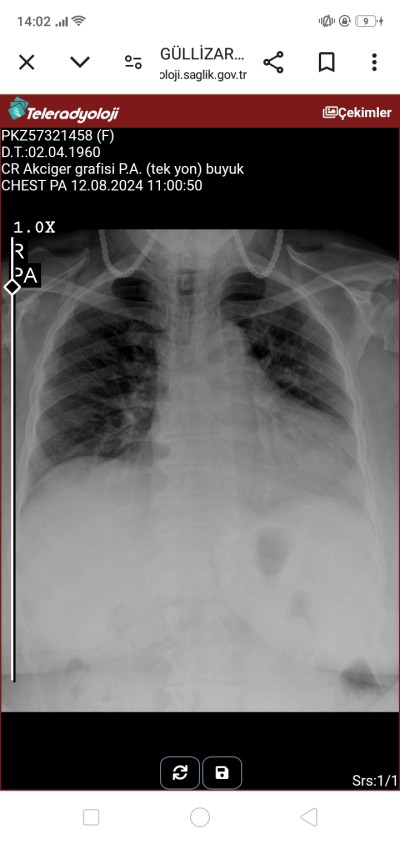

Akciğer grafisi anlayan var mi kizlar

Belki bilen çıkar randevu suremizee var daha

sanki orda bir leke var gibi

Ne için cektirmistiniz ne şikayetiyle gittiniz

Nefes yetersizliği